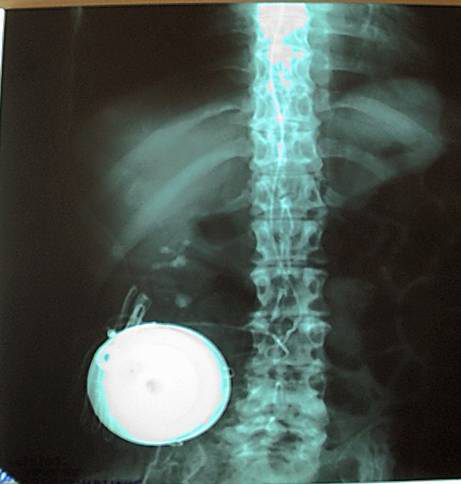

Χρησιμοποιείται για τη θεραπεία σοβαρής σπαστικότητας εγκεφαλικής ή νωτιαίας προέλευσης (τραυματική βλάβη νωτιαίου μυελού, κρανιοεγκεφαλικές κακώσεις, σκλήρυνση κατά πλάκας, εγκεφαλική παράλυση), όταν τα άλλα αντισπαστικά φάρμακα δεν είναι αποτελεσματικά ή ανεκτά. Πραγματοποιείται υποδόρια εμφύτευση αντλίας στην κοιλιακή χώρα, ενώ η έγχυση της μπακλοφένης γίνεται μέσω καθετήρος στην οσφυϊκή χώρα που η τελική άκρη του εισέρχεται ενδοραχιαία. Η μέθοδος είναι αποτελεσματική, ασφαλής και καλά ανεκτή, ενώ η δόση μπορεί εύκολα να ρυθμίζεται και να τροποποιείται, ανάλογα με τον βαθμό της σπαστικότητας.

ακτινολογική εικόνα τοποθετημένης αντλίας μπακλοφένης